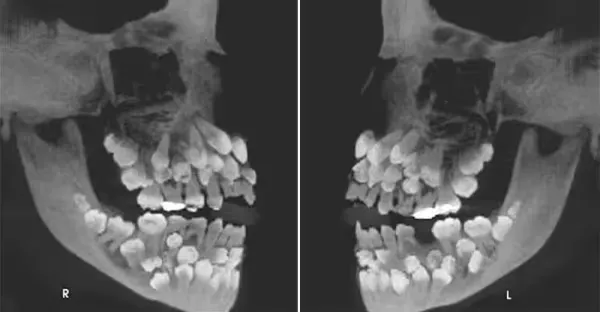

女童拔乳牙...X光驚見「81顆牙塞滿嘴」嚇壞牙醫:罕見

女童拔乳牙...X光驚見「81顆牙塞滿嘴」嚇壞牙醫:太罕見

呂純弘 • 130次觀看